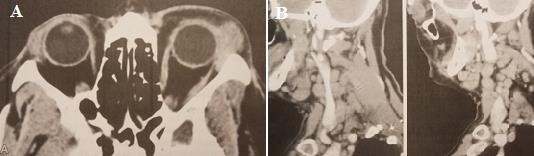

Hình 1.11. Cắt lớp vi tính u lympho ác tính tuyến lệ

A. Mắt trái có khối u vùng hố lệ. B. Hạch lympho vùng cổ Nguồn: Coupland và cộng sự (1998)48